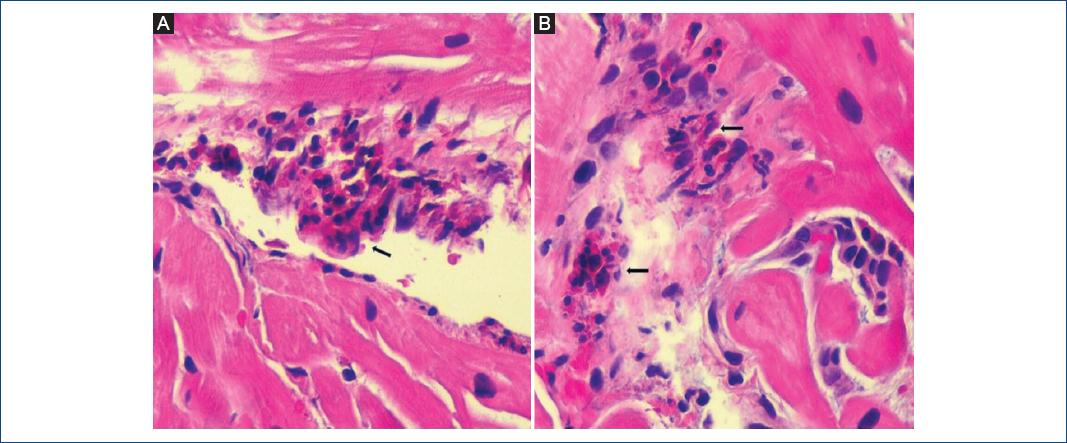

Macroscópicamente se presenta como una endocarditis verrucosa (fig. Viruses account for most cases of myocarditis or inflammatory cardiomyopathy, which could induce an immune response causing inflammation even when the pathogen has been cleared. Se estableció el diagnóstico de miocarditis por dengue grave y se inició tratamiento con corticoides utilizando metilprednisolona (500 mg en bolo i.v. Cardiovascular magnetic resonance, systemic lupus erythematosus, myocarditis, delay enhancement. Información actualizada sobre vacunación para. Seguido de 250 mg tres veces al día durante 3 días). Murine models of enteroviral myocarditis suggest viral myocarditis is characterized by 3 phases acute: Infarto de miocardio• implantación válvula cardiaca 14. Estas verrugas son pequeñas formaciones de 1 a 3 milímetros, rojizas, vítreas, adherentes, que con mayor frecuencia se producen en el borde cierre de. Acute injury of the myocytes, induced by virus replication leading to myocyte necrosis this exposes the intracellular antigens (e.g. Es importante recordar que la miocarditis suele estar infradiagnosticada. Se sustituyó oseltamivir por ribavirina. 16 vallés belsué 1974 23 14/9 se presentan los hallazgos cineangiográficos del ventrículo izquierdo en 23 casos de mch obstructiva.

Cardiovascular magnetic resonance, systemic lupus erythematosus, myocarditis, delay enhancement. Los anticuerpos igm e igg específicos para el virus del dengue fueron positivos. Puede sentirse en el cuello, el hombro, la espalda o el abdomen. Myocarditis is defined as an inflammatory disease of the heart muscle and is an important cause of acute heart failure, sudden death, and dilated cardiomyopathy. Myocarditis is infrequent (10%) and may evolve Con frecuencia, aumenta con la respiración profunda y al acostarse en posición horizontal; Acute injury of the myocytes, induced by virus replication leading to myocyte necrosis this exposes the intracellular antigens (e.g. La miocarditis es la enfermedad inflamatoria del miocardio diagnosticada por criterios histológicos, inmunológicos e inmunohistoquímicos, y refleja la respuesta inmunológica del huésped tras la exposición a un antígeno externo (microbiológico u otro) o interno (autoinmunidad frente a antígeno propio).